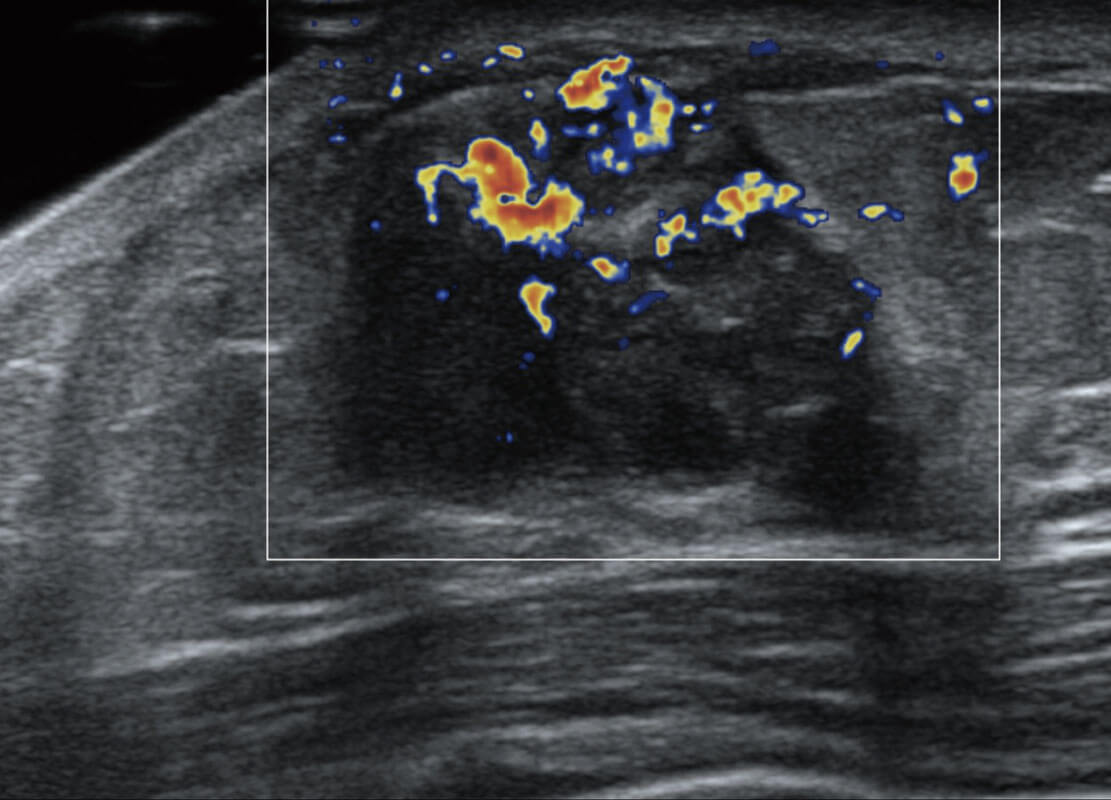

新生儿肝血管癌

P60搭载宽频带线阵探头、宽景成像、弹性成像技术,为您提供乳腺应用方案。P60支持高频相控阵探头、线阵探头、腹部高频探头、腹部微凸探头等,丰富的探头群搭载敏感的彩色血流成像,适用于新生儿多种脏器检测要求,满足新生儿筛查需求。